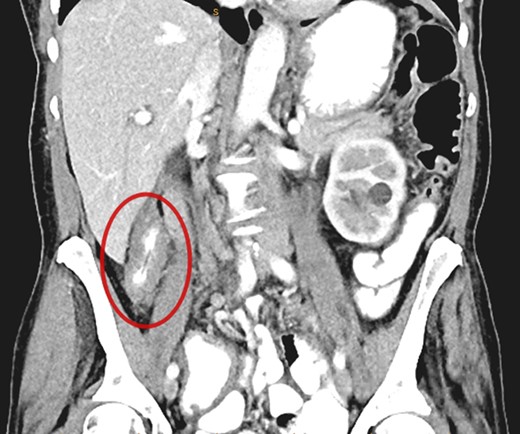

Submucosal biopsies from ascending colon unexpectedly demonstrated metastatic carcinoma consistent with female genital tract origin—CK7 positive; CK20 negative; PAX-8/WT-1/ER/CA125 all positive. A PET/CT was performed on the basis of the histological findings, which demonstrated intense FDG-avidity in the known site of disease in the ascending colon (Figs 2 and 3), as well as a separate focus of increased metabolism in the left pelvic side-wall (Fig. 4), which was presumed to represent an ovarian primary. There was no evidence of nodal or peritoneal disease, however, note was made of mild bilateral hydroureter without clear transition point. CA125 was 118 U/mL (Ref. range 0–35).

Axial PET showing separate focus of avidity in left pelvic side-wall.